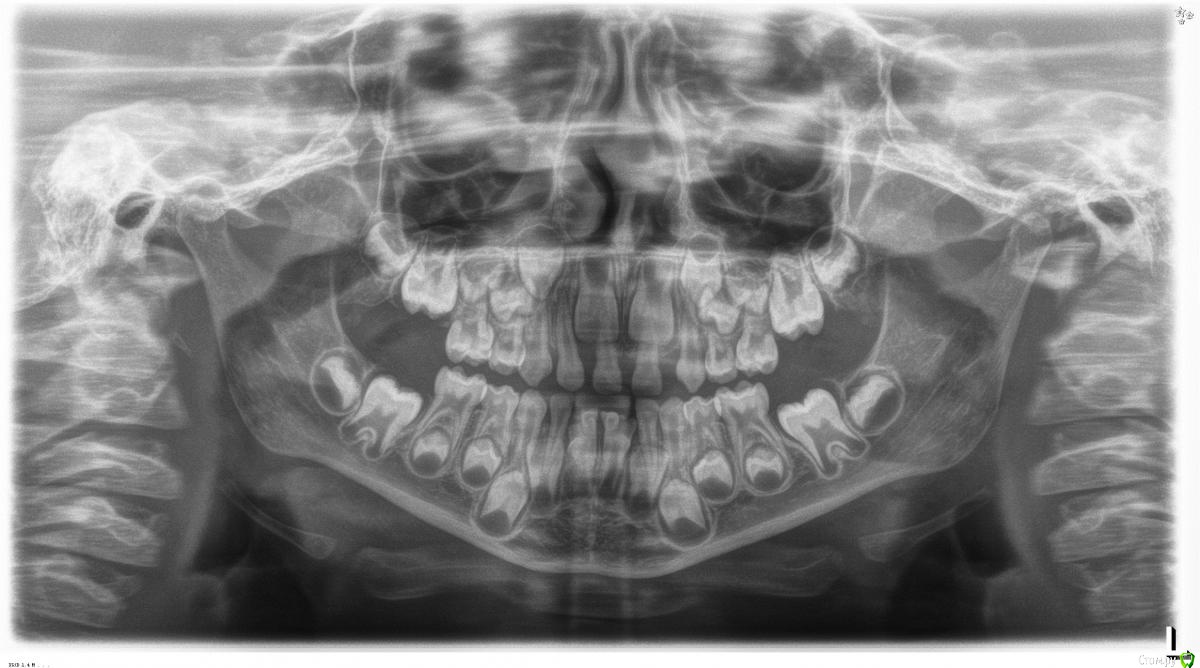

Давлетшин Опубликовано 8 ноября, 2016 Поделиться Опубликовано 8 ноября, 2016 (изменено) Здравствуйте коллеги, вопрос может и простой для вас , но если сориентируете то большое спасибо.Пац 5 лет, обнаружена адентия 62,12,22 зубов. что делать в дальнейшем?1) перемещать клыки на место резцов?2) создавать место для резцов с замещающей пластинкой и имплантацией в дальнейшем?3) может еще варианты? 4) рано еще говорить.Сам доктор детский, прохожу обучение в ординатуре. Изменено 8 ноября, 2016 пользователем Д А Р Ссылка на комментарий

Opdihatop Опубликовано 8 ноября, 2016 Поделиться Опубликовано 8 ноября, 2016 Я всегда делаю по 2-му варианту, по многим причинам. Но сейчас я бы еще не вмешивался... пусть 11, 21 поменяются... Ссылка на комментарий